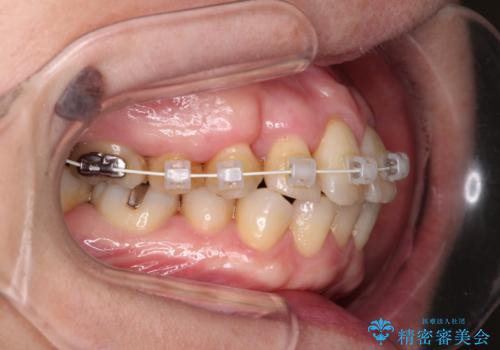

- 矯正装置

- 審美装置

- 治療期間

- 9ヶ月

- 治療回数

- 10-30回